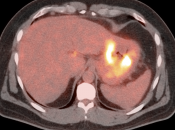

• Distant Disease: Most commonly to the liver, peritoneum, lung and bone.

The difficulty with PET/CT imaging and gastric cancer is that it is both easy to overlook and easy to over-call.

Normal FDG uptake involving the stomach can be extremely variable. It is not uncommon to see diffuse intense uptake throughout the entire stomach or intense uptake limited to only a segment of the stomach (fundus, body or antrum).

• Focal or regional hypermetabolic activity is accompanied by at least the suggestion of associated wall thickening (often difficult to assess if the patient’s stomach is suboptimally distended with water or oral contrast);

• Obviously, signs of associated metastatic disease on the scan give the radiologist much greater confidence in reporting a suspected primary gastric lesion.